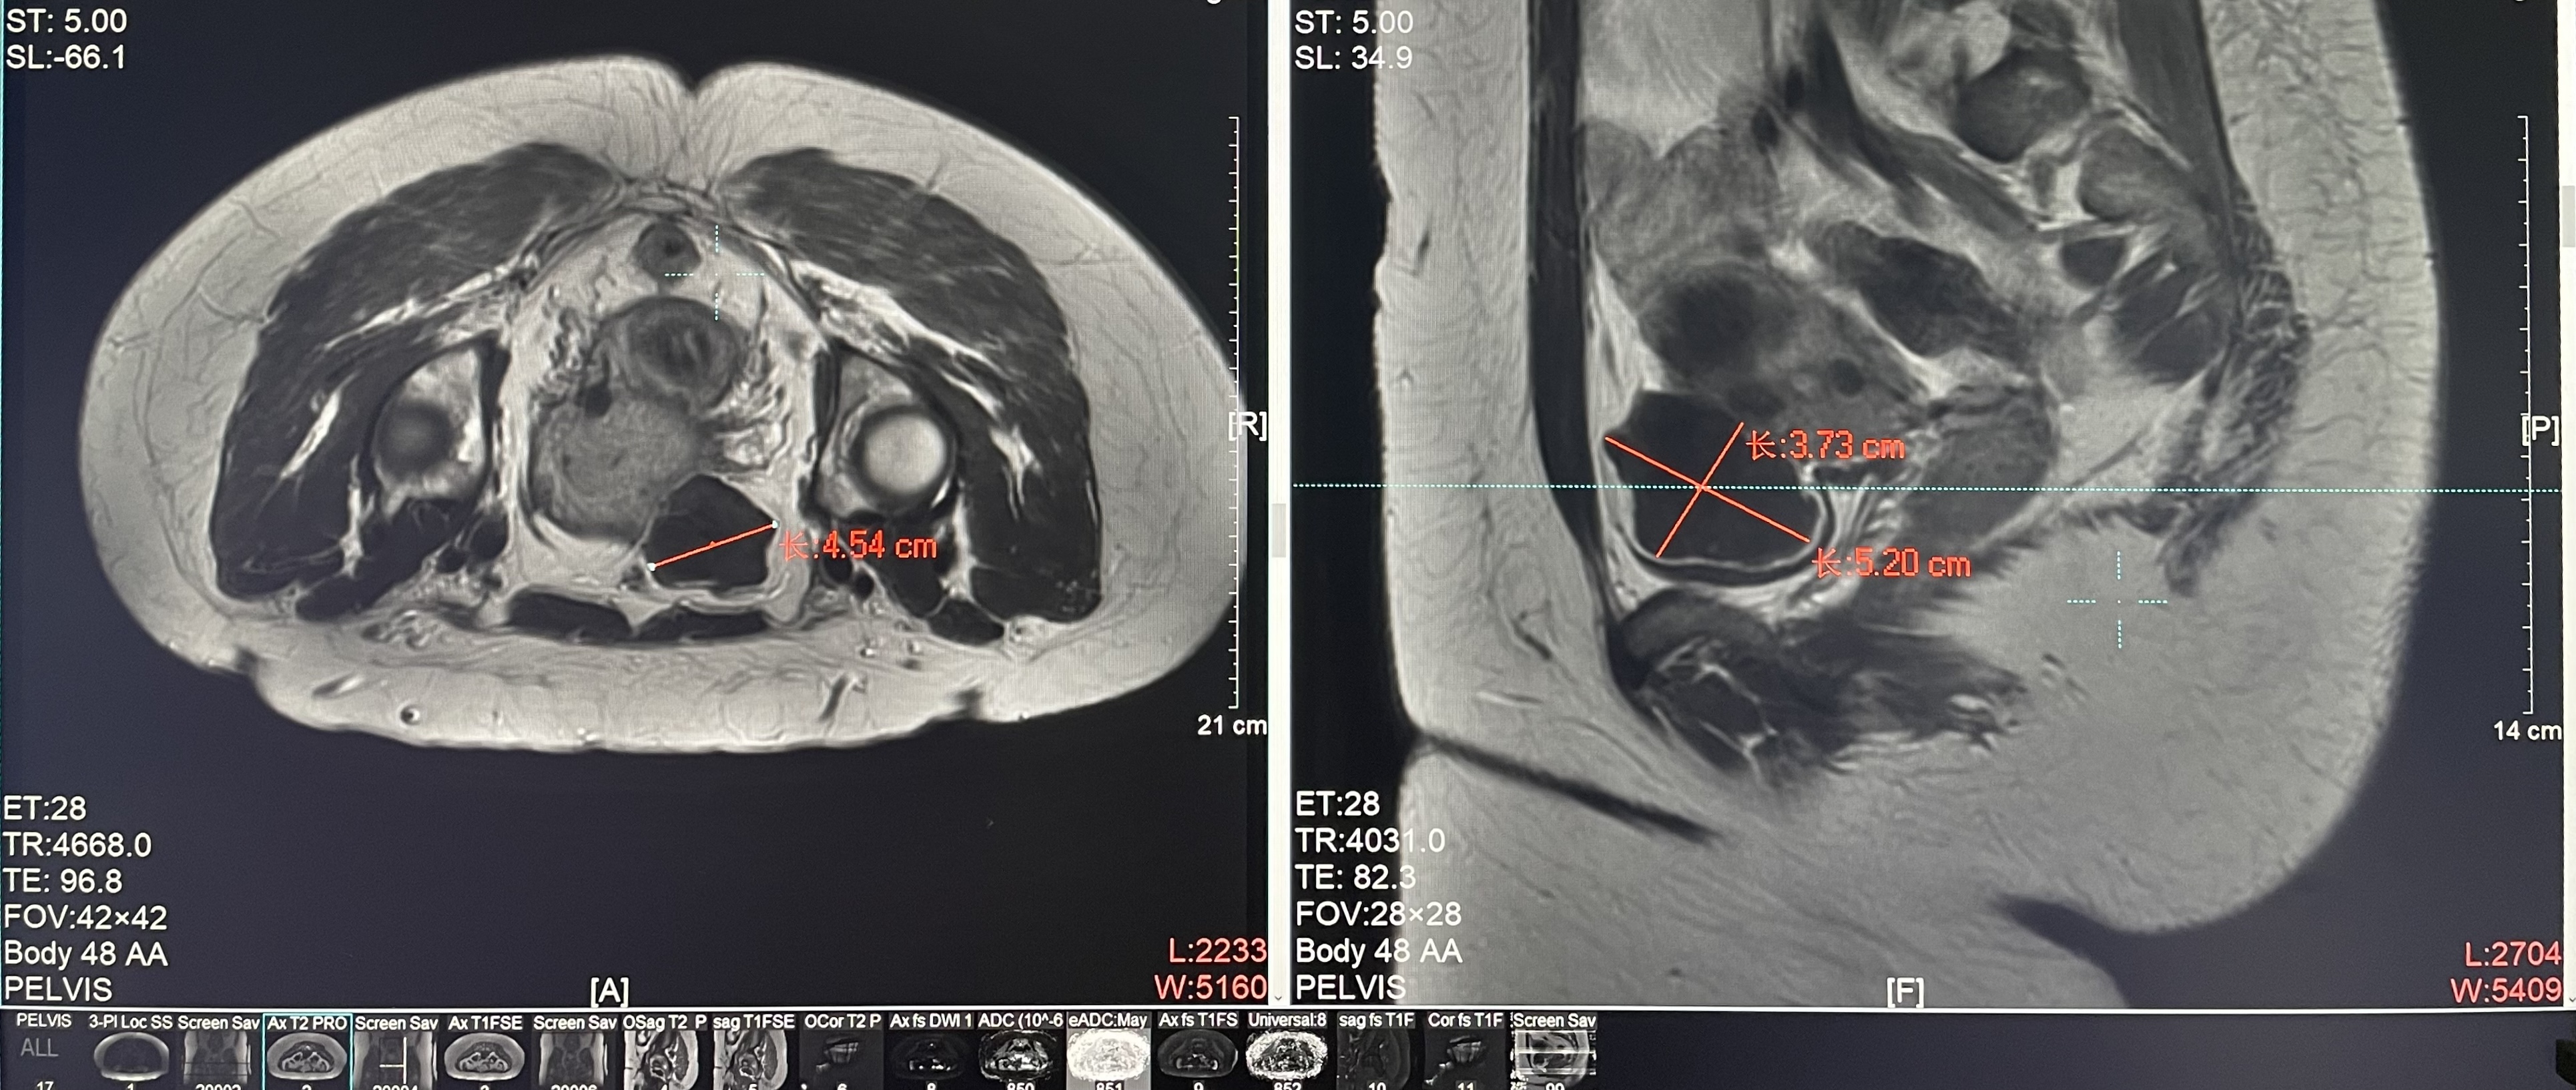

Diagnosis: Uterine fibroids

Tumor size: about 45*52*38mm